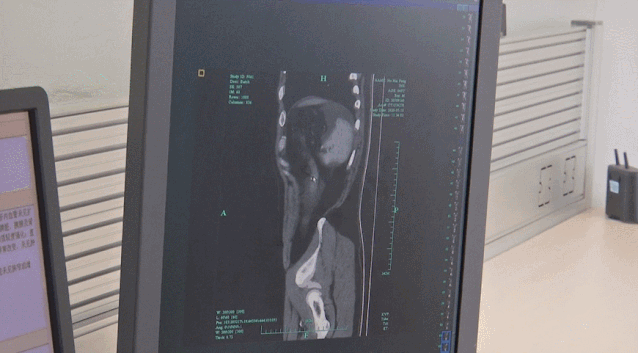

El hombre se despertó con fuertes dolores abdominales y tuvo que ser ingresado en el Hospital Popular Zhuji en Zhejiang, este de China, donde una tomografía computarizada reveló que su vejiga había estallado en tres partes. Los médicos calificaron sus lesiones como “potencialmente peligrosas”.